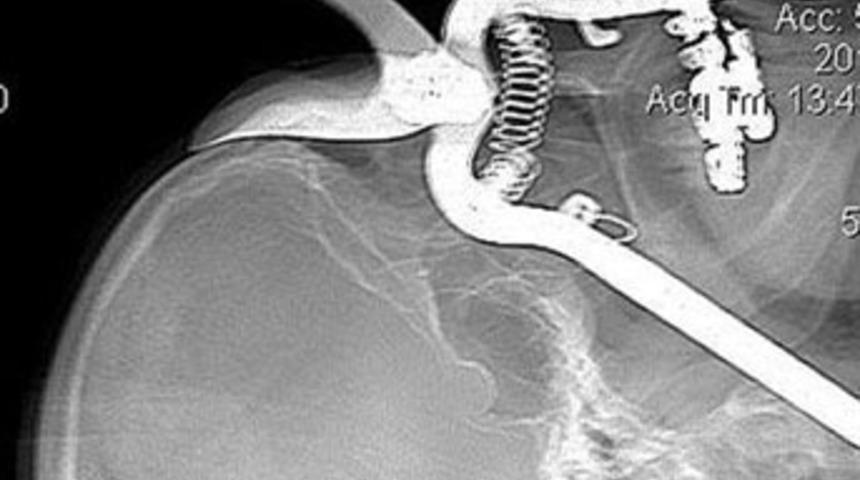

ABD'nin Tucson kentinde yaşayan 86 yaşındaki Leroy Luetscher'in üzerine düştüğü bahçe makası, göz çukurundan girerek boğazına kadar ilerledi.

İşe devam etmek isteyen yaşlı adam, makası düştüğü yerden almak için eğildi. Ancak bir anda dengesini kaybederek yüz üstü makasın üzerine düştü. Makasın elle tutulan kısmı, luetscher'in göz çukurundan içeri girerek boğazındaki beyne kan götüren damarlara saplandı.

Yaşlı adam yakınları tarafından makas çıkarılmadan derhal Arizona Üniversitesi Hastanesi'ne kaldırıldı. Ameliyatla bahçe makasını çıkaran doktorlar, Luetscher'in göz çukurunu da metal kafes ile tedavi ederek yaşlı adamın gözünü kurtarmayı başardı.